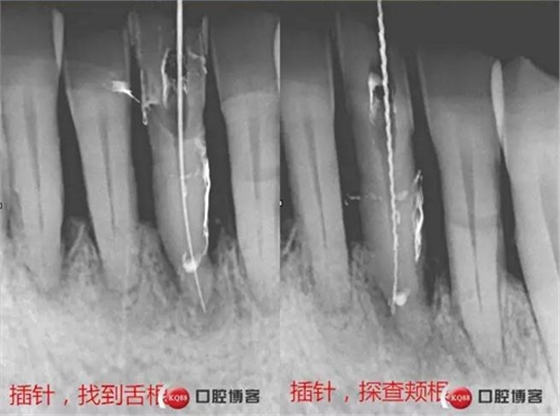

處理:上橡皮障,31開(kāi)髓,測(cè)工作長(zhǎng)度17mm,含氯沖洗液沖洗,機(jī)擴(kuò)至04錐度30#,超聲蕩洗,一次性根充。33-43牙齒鄰接處super bond粘結(jié)固位,行松牙固定。調(diào)合。拍根充術(shù)后片,未達(dá)根尖,懷疑遺漏根管,去除根充物后,繼續(xù)探查根管,找到舌側(cè)根管,測(cè)長(zhǎng)度20mm,時(shí)間原因,未行擴(kuò)根,氫氧化鈣暫封。

處理:31去暫封,手用銼疏通根管,沖洗,機(jī)擴(kuò)至04錐度30#,超聲蕩洗,封維塔,拍片。